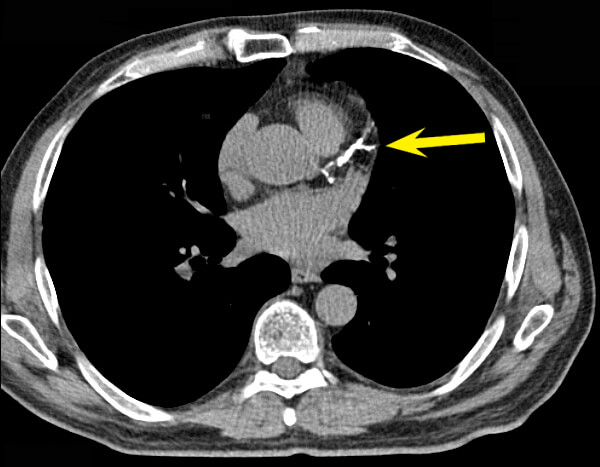

And third, while it might have sounded like a good idea to remove calcium from atherosclerotic plaques back in the 1950s, seven decades of subsequent research cast this idea in serious doubt. It’s now clear that the bulk of the calcium deposits in atherosclerotic plaque — the part that you readily see on a coronary calcium scan — don’t coincide with the lesions that go on to rupture and trigger heart attacks and strokes. The value of the coronary calcium scan is not that it reveals the specific atherosclerotic lesions that are likely to kill you, but that the overall extent of calcified plaque gives a convenient index of a person’s total burden of advanced lesions, and thus the risk to the patient. From this comes the saying, “Coronary calcification identifies the vulnerable patient rather than the vulnerable plaque.”